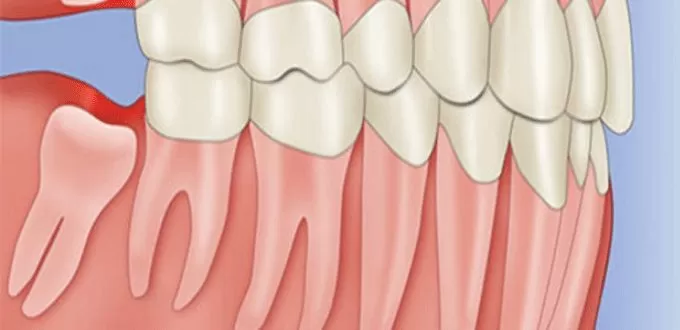

Phẫu thuật làm dài thân răng cũng có thể được thực hiện trước điều trị phục hồi hoặc thẩm mỹ. Ví dụ trong trường hợp sâu răng dưới nướu hoặc cấu trúc răng còn lại quá ít không đủ khả năng lưu giữ phục hình. Trong những trường hợp này, phẫu thuật sẽ bộc lộ nhiều hơn cấu trúc răng để có thể tiến hành điều trị phục hồi.